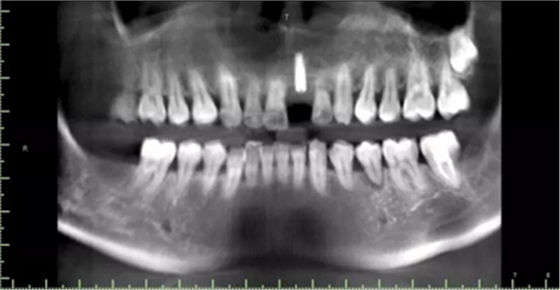

現(xiàn)病史:患者牙周病五年余,牙石(+++)、牙周??;15、26牙齲齒;,今就診我院,要求21牙種植修復(fù)。

1.術(shù)前CT

術(shù)后CT